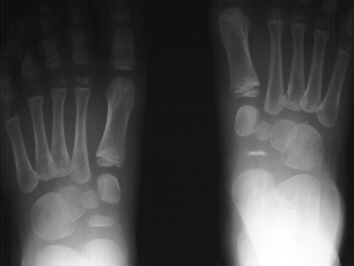

An

x-ray at six months showed a very thinned navicular with irregular

ossification. The mother is told that this is normal and in the

long term there will be no disability from this process.